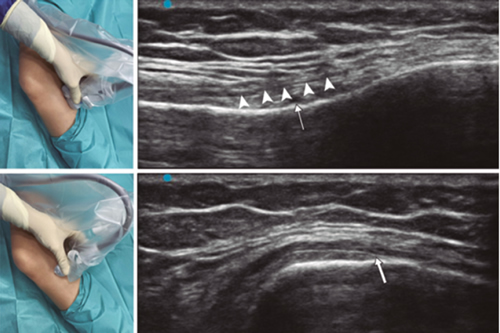

Figure 3

Figure 4

Figure 5